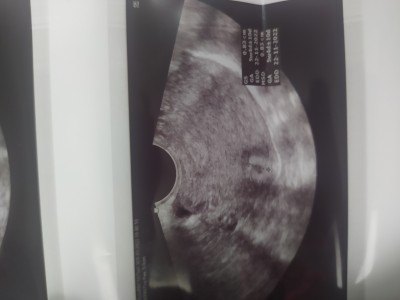

Merhaba hanimlar. Adetimden 10 gun sonra ultrasonda sadece 4 haftalik kese gozuktu. Normalmi?

Normal tabiki daha çok küçük kesen bile iyi gozukmus bu haftada iki hafta bekle bebek anca gözükür

Daha çok küçük kese bile zor görünür bu haftada. Bebek ve kalp atışı için 7. Haftada gidersen görürsün inşallah

Ben de öğrendiğimde 5+3 dü. Bundan biraz daha büyüktü ama aynı böyle görünüyordu (12 mm idi)